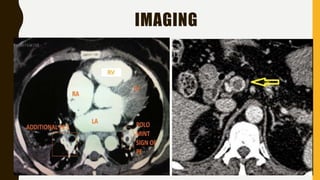

• CT pulmonary angiography (CTPA) will show filling defects

within the pulmonary vasculature with acute pulmonary emboli.

• When the artery is viewed in its axial plane the central filling

defect from the thrombus is surrounded by a thin rim of

contrast, which has been called the Polo Mint sign.

IMAGING

RV